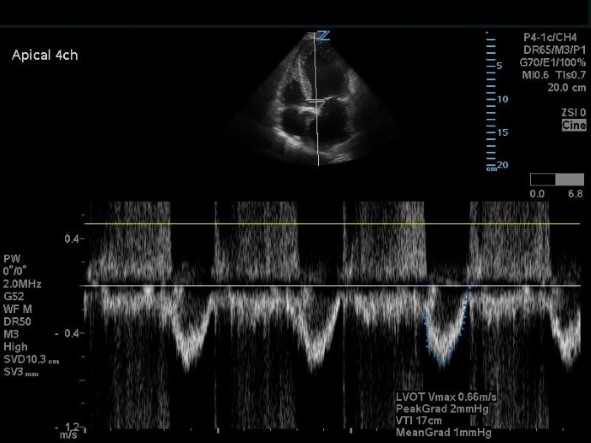

- Switch to pulse wave doppler (PWD) in the same A5CH view and place the doppler gate through the LVOT. Trace the obtained waveform in the same fashion to calculate the LVOT VTI. To also calculate cardiac output, measure the heart rate during this step using the machine preset.

Figure 6. Apical five-chamber view with pulse wave doppler on the LVOT.